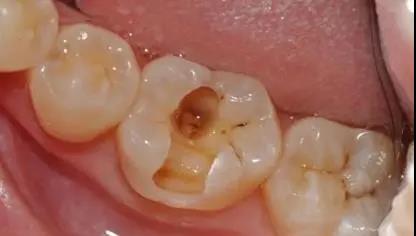

这些酸对牙齿外层的牙釉质具有酸蚀作用,由此牙齿开始变色,时间一长甚至会形成蛀牙龋洞。

▶ 被“蛀出洞”的牙齿

牙齿邻接处变色

牙齿邻接处缺损,出现龋洞